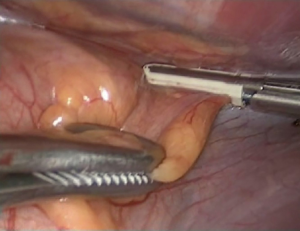

Then the thymus is dissected of the sternum by opening the mediastinal pleura along the right internal mammary artery/vein under the sternum (Figure 5). The dissection from the right side parallel to the phrenic nerve enables visualization of the superior vena cava and junction of both innominate veins clearly becomes visible V体育官网. The most dangerous and accident inviting part of this operation is the dissection of the upper poles. By gentle traction on both superior poles of the thymus could be dissected and under direct visualisation (Figure 6). The superior poles dissection is best provided with gentle force applied caudally, with the use of countertraction dissection towards thyroid gland. The arterial and venous branches from the internal mammary vessels could be identified and clipped. The major thymic veins may be at different numbers and locations could be dissected and divided by clipping (Figures 7,8).

The specimen is removed with an Endo bag (Figure 12). The mediastinum is carefully inspected or any foreign body or any remaining fatty mediastinal tissue or hemostasis. One 10 mm drain is placed through the most anterior port across the mediastinum to drain the both chest (Figure 13).